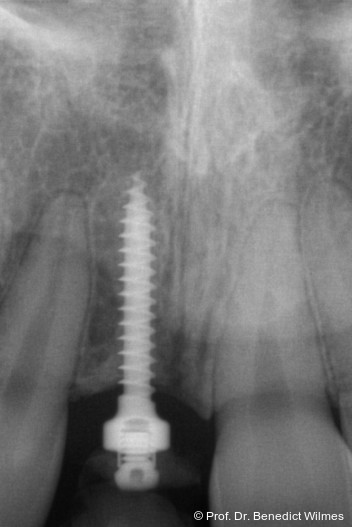

Ein 14-jähriger Patient wurde bei Aplasie der beiden oberen seitlichen Schneidezähne mit dem Ziel der beidseitigen Lückenöffnung kieferorthopädisch therapiert (Abb. 1a+b). Zum Ende der kieferorthopädischen Behandlung wurden zwei Miniimplantate in Regio 2er als temporärer Zahnersatz inseriert (Benefit System, PSM, 2 x 13 mm, Abb. 2a+b). Nach Abdrucknahme wurden Kronen auf den Peek-Abutments modelliert und diese mit Kunststoff auf die Abutments geklebt (Abb. 3a–d). In den Abbildungen 3 und 4 sind die klinischen und röntgenologischen Nachkontrollen innerhalb der nächsten achteinhalb Jahre dokumentiert. Man erkennt einen sowohl in der Höhe als auch in bukkopalatinalen Breite verbleibenden gesunden Knochen ohne Anzeichen einer Atrophie. Im Alter von 23 Jahren wurden die definitiven Implantate ohne die Notwendigkeit einer Augmentation eingesetzt (Abb. 5) und nach Einheilung prothetisch versorgt (Abb. 6a–e und Abb. 7a–c).